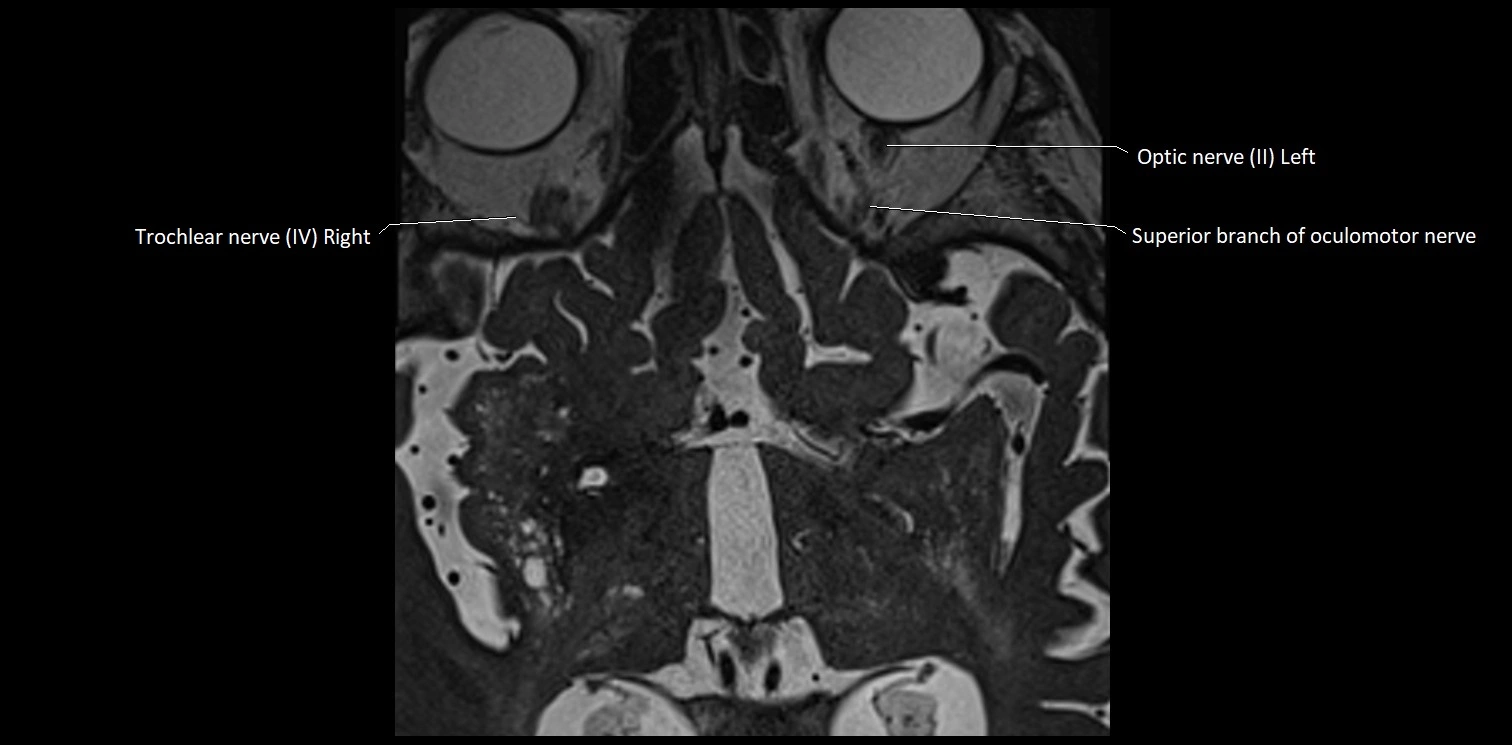

MRI Appearance

• The abducens nerve is a small, thin, linear structure

• Best visualized on high-resolution T2-weighted 3D MRI sequences (e.g., FIESTA or CISS)

• Seen as a hypointense (dark) line running from the brainstem at the pontomedullary junction, traversing the prepontine cistern, and entering Dorello’s canal under the petrosphenoidal ligament, then into the cavernous sinus, and finally the orbit

• May be challenging to visualize in standard MRI due to its small size

• Pathology may be inferred by absence, displacement, or enhancement of the nerve

MRI images

image